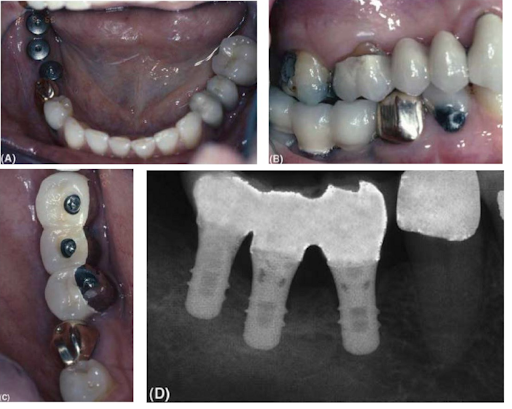

Khớp cắn được kiểm tra trên một cầu răng dưới được implant nâng đỡ. (A) Giấy cắn được dùng để đánh dấu sự chạm khớp ban đầu dưới lực cắn nhẹ. (B) Các dấu chạm rõ nhất xuất hiện trên răng tự nhiên và cầu implant (thứ hai và thứ ba từ phía sau) chỉ chạm nhẹ. (C) Shim stock được dùng để xác nhận phục hình implant chạm khớp dưới lực cắn mạnh.

Sau đó nên sử dụng shim stock, và khi chạm khớp nhẹ, cầu răng trên implant sẽ không giữ shim stock nhưng răng thì giữ được. Khi bệnh nhân cắn chặt hơn thì cầu răng sẽ giữ được shim stock giống như răng. Lý tưởng nhất là các vùng chạm khớp nên nằm càng gần tâm của implant càng tốt để lực truyền thẳng xuống trục của implant khi tải lực. Nhịp với nên chịu lực càng ít càng tốt.

Sau khi hoàn thành, chụp phim quanh chóp tất cả các implant để xác nhận đã gắn khít sát và làm một hướng dẫn sau này cho việc đánh giá mức độ xương viền.

Một cầu răng sau nâng đỡ bởi implant Straumann: (A) Ba abutment lành thương có thể nhìn thấy. (B) Cầu răng hoàn thành. (C) Nhìn từ mặt nhai-vít được sử dụng. (D) Phim quanh chóp chụp khi kết thúc điều trị.